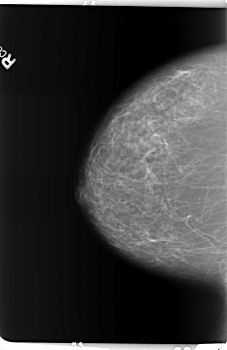

B_3154_1.RIGHT_CC

RIGHT_CC LINES 5936 PIXELS_PER_LINE 3856 BITS_PER_PIXEL 12 RESOLUTION 50 NON_OVERLAY